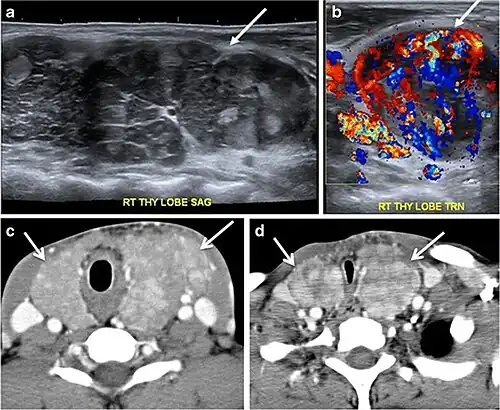

Fig. 5. A poorly differentiated invasive left thyroid mass in a 58-year-old female patient. a Sagittal greyscale neck ultrasound shows a large hypoechoic lesion with macro-calcification and micro-calcification. b Sagittal colour Doppler ultrasound shows left internal jugular vein filling defect with detected internal vascularity suggestive of tumour thrombus. c Enhanced axial and coronal CT scans of the neck show heterogeneously enhancing large lesion replacing the left thyroid lobe and extending to the isthmus and the medial aspect of the right thyroid lobe (white arrow). The mass and the conglomerate lymph nodes measure 12.5 × 7 × 5.8 cm (white arrows). d, e Axial enhanced CT scans show enlarged left cervical nodes (white arrow) and left internal jugular vein (IJV) thrombus (black arrows). Note the IJV distention and central enhancing portion in the upper cut (black arrow in e) concerning the tumour thrombus. f, g Enhanced axial CT scan of the upper chest demonstrate a mass extension into the retrosternal area, left tracheoesophageal groove, and posterior to the trachea (white arrows in f). There are multiple bilateral pulmonary nodules (white arrows in g).[1]